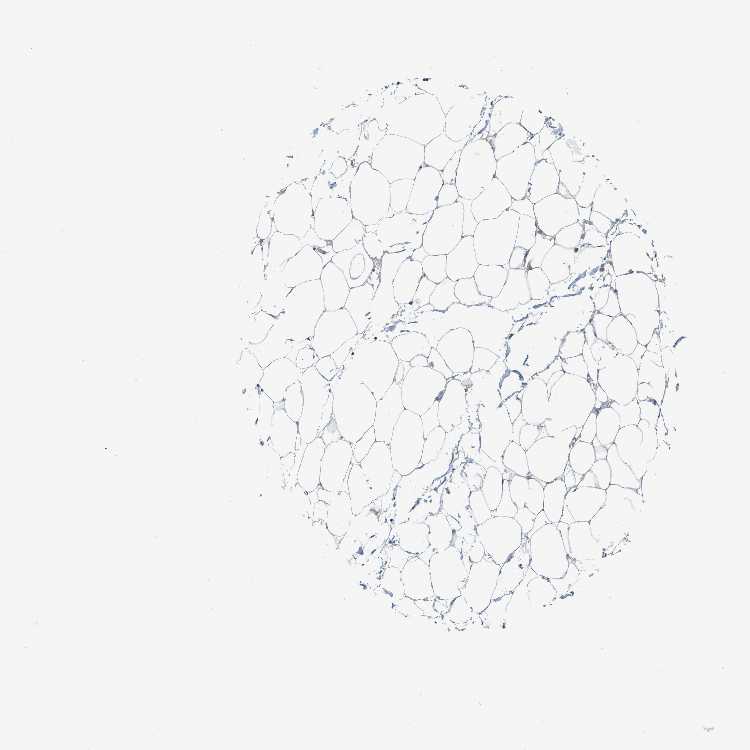

SOFT TISSUE 1 - Antibody stainingi

Antibody staining in the annotated cell types in the current human tissue is reported as not detected, low, medium, or high, based on conventional immunohistochemistry profiling in selected tissues. This score is based on the combination of the staining intensity and fraction of stained cells.

Each image is clickable and will lead to virtual microscopy that enables deeper exploration of all samples and also displays staining intensity scores, fraction scores and subcellular localization as well as patient and tissue information for each sample.

Antibody HPA022537Antibody HPA024241

Fibroblasts Not detectedNot detected

SOFT TISSUE 2 - Antibody stainingi

Peripheral nerve High-